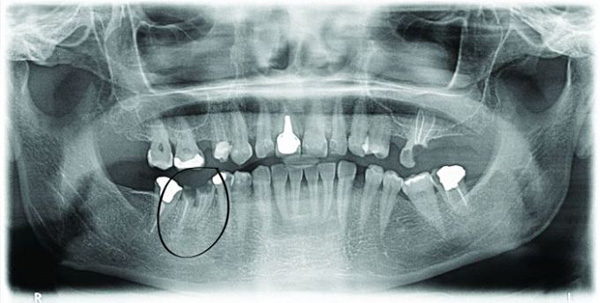

From the next OPG image the infection is visible (small shadow) and it is a potential risk for the successful loading of the implant. The possible lack of bone caused by the infection is resolved with bone augmentation procedure performed using the artificial bone materials such as BoneCeramic, BioOss, ecc. However, the infection should not be a problem since with modern technologies and instruments it can be easily resolved. photo No. 2.